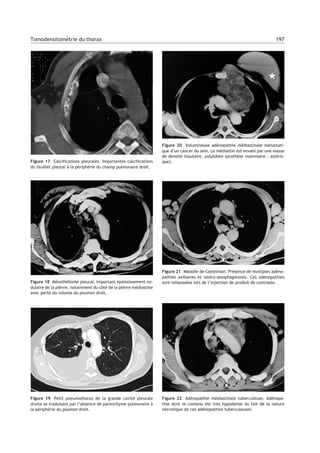

Figure 20 Volumineuse adénopathie médiastinale métastati-

que d’un cancer du sein. Le médiastin est envahi par une masse

de densité tissulaire, polylobée (prothèse mammaire : astéris-

que).

Figure 21 Maladie de Castelman. Présence de multiples adéno-

pathies axillaires et latéro-œsophagiennes. Ces adénopathies

sont rehaussées lors de l’injection de produit de contraste.

Figure 22 Adénopathie médiastinale tuberculeuse. Adénopa-

thie dont le contenu est très hypodense du fait de la nature

nécrotique de ces adénopathies tuberculeuses.